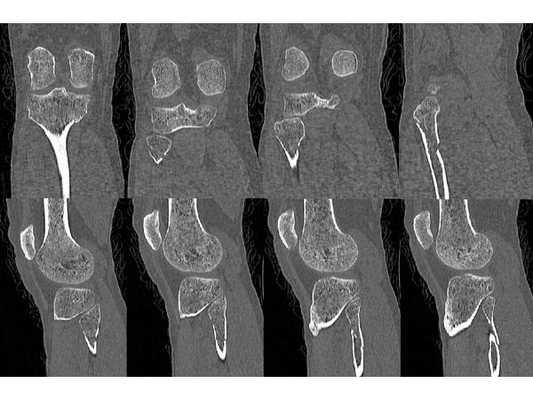

- Компьютерная томография правой голени.

Закрытый оскольчатый перелом внутренней лодыжки правой голени со смещением отломков. Закрытый перелом верхней трети малоберцовой кости правой голени. Повреждение дистального межберцового синдесмоза ( соединения большеберцовой и малоберцовой костей) . Подвывих стопы кнаружи (Maisonneuve-type fracture).

После обследования и уменьшения отёка мягких тканей на четвёртые сутки с момента травмы больному проведено оперативное вмешательство. Под спинномозговой анестезией выполнена открытая репозиция перелома внутренней лодыжки правой голени спицами и стягивающей проволочной петлёй, фиксация дистального межберцового синдесмоза стягивающей петлёй с упорными металлическими площадками.